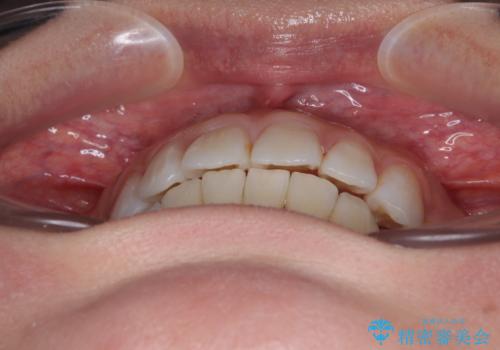

- 上下前歯の後戻りを気にして来院された患者様です。

インビザラインでの治療を希望されていて、デコボコの程度が中等度であり、安価なパッケージにて対応可能と判断されたため、インビザライン・モデレートを用いて矯正治療を行うこととしました。

インビザライン・モデレートは、製作できるアライナーの枚数に制限があるため、移動可能な量に限りがあるものの、インビザライン・ライトよりも枚数が多いため、幅広い症例に対応可能です。